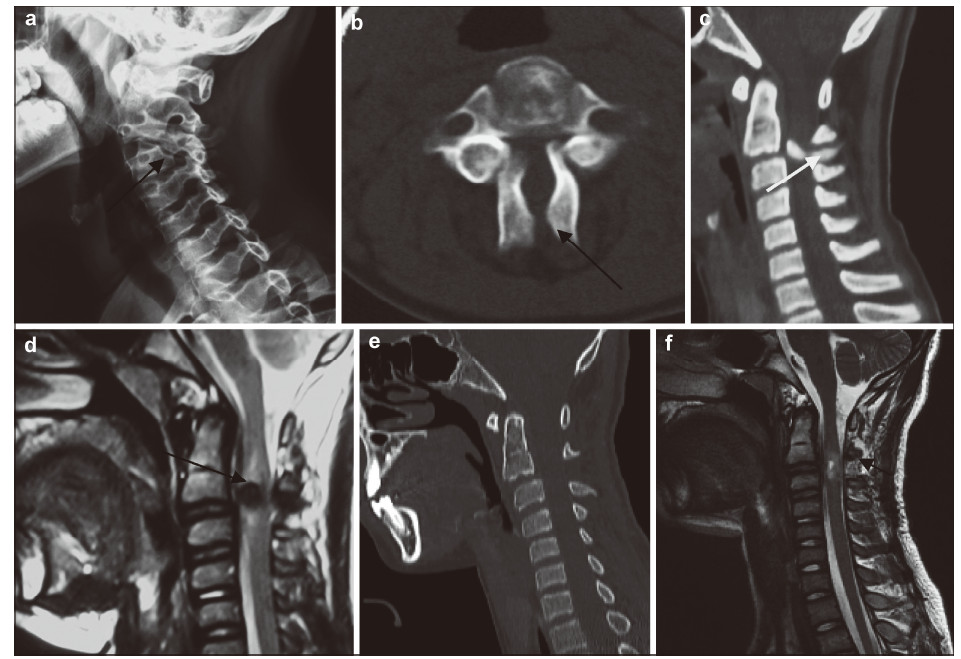

| Figure 2 A 26‐year‐old man presented with bilateral C3 spondylolysis. (a) Lateral view plain radiography showing a hypoplastic articular mass and spinal process at C2(black arrow).(b) Iodine contrast CT showing bilateral clefts between the articular pillar and the facets of C3 as well as spina bifida (white arrow). |

| Figure 3 A 14‐year‐old boy presented with bilateral C3 spondylolysis.(a) Oblique view plain radiography showing a cleft of the articular pillar (arrow).(b) On axial CT,the lateral mass at C3 was discontinuous,with typical features of spina bifida (arrow).(c,d) A bony density (white arrow) and low cord signal (black arrow) change was observed at the spondylolytic level.(e,f) Follow‐up CT showed the bony density had disappeared and MRI showed a slightly high cord signal (arrow). |